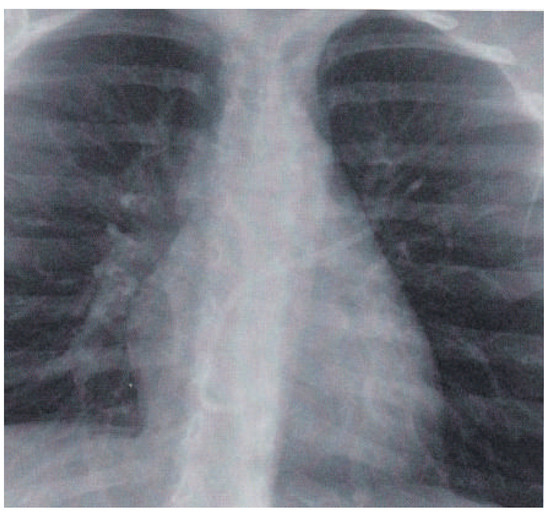

Cardiac Sarcoidosis with Coeliac Disease

by Stéphane Fournier, Julien Regamey, Samuel Rotman, Etienne Pruvot and Roger Hullin

Cardiovasc. Med. 2016, 19(4), 128; https://doi.org/10.4414/cvm.2016.00412 - 20 Apr 2016

This case of cardiac sarcoidosis started with manifestation of a complete atrioventricular block in a 42-year-old female without other cardiac dysfunction. Two years later, the patient presented with acute heart failure symptoms at the Emergency Department. Echocardiography at admission showed thinning and hyperdensity [...] Read more.

This case of cardiac sarcoidosis started with manifestation of a complete atrioventricular block in a 42-year-old female without other cardiac dysfunction. Two years later, the patient presented with acute heart failure symptoms at the Emergency Department. Echocardiography at admission showed thinning and hyperdensity of the basal interventricular septum, which is a rare but typical echocardiographic sign of cardiac sarcoidosis. Endomyocardial biopsy, positron emission tomography–computed t omography and transbronchial biopsy confirmed the clinical suspicion of sarcoidosis. Of note, the patient also had coeliac disease, which can occur conjointly with sarcoidosis. After 5 months of immunosuppressive treatment with methylprednisolone and azathioprine the burden of inflammatory lesions was significantly reduced and the patient had improved to New York Heart Association class I. Full article